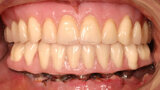

Fig. 10. Prótesis híbrida inmediata con 10 años de evolución y Rx Control a los 10 años.